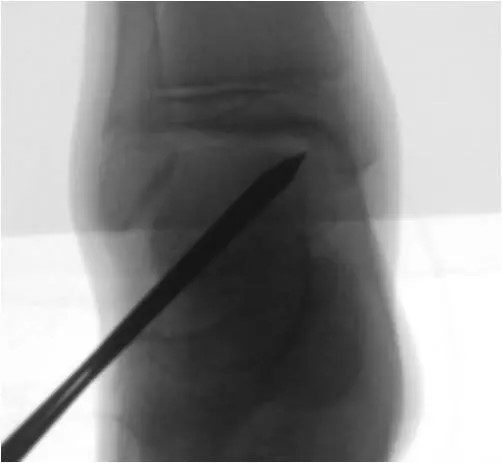

Retrograde Anbohrung

Kleine knöcherne Defekte ohne Hinweis auf eine Schädigung des darüber liegenden Knorpels können durch eine Anbohrung behandelt werden. Die Anbohrung erfolgt häufig mit Drähten oder einem dünnen Bohrer der abhängig von der Lokalisation von fußwärts eingebracht wird. Damit lassen sich kleine zystische Veränderung des Knochens und kleinere knöcherne Defekte häufig adressieren.